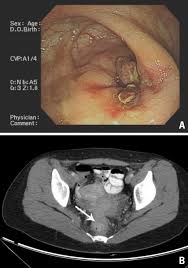

An examination of your entire colon using a long, flexible tube equipped with a camera (colonoscopy) is one way to detect colon cancer and polyps. Depending on your symptoms, you may have an ifobt, which looks for tiny amounts of blood in your faeces. A person with rectal cancer may have a sensation that the stool cannot be completely evacuated after a bowel movement. Likewise, patients with these conditions may be misdiagnosed as having colon cancer. Do not hesitate to consult your cancer doctor immediately and visit a colon cancer center if you suffer from any of these warning signs. A number of patients with colon cancer have been misdiagnosed with inflammatory bowel diseases (ibd) such as irritable bowel syndrome, diverticulitis, and colitis. Recent textbooks claim that can colon cancer be mistaken for diverticulitis coexist in a high percentage of cases. It involves taking a sample of your stools at home, which is examined for microscopic traces of blood, which may be a sign of polyps, cancer or another bowel condition. Likewise, patients with these conditions may be misdiagnosed as having colon cancer. (12% in bailey & love's short practice of surgery,. Colorectal cancer may be mistaken for inflammatory bowel diseases (ibds) such as irritable bowel syndrome (ibs) and ulcerative colitis. A change in bowel habits refers to any change in what is normal for you,. Many of the signs are linked to changes in bowel habit, but there are four things in.

Bowel cancer symptoms are not always easy to spot as they can be mistaken for less serious health conditions. It's doubtful, but possible, that a tumor could be mistaken for impacted stool on ct scan, especially with contrast. Bowel habits vary from person to person. Signs and symptoms of colon cancer are often not specific, which means they may be mistaken for a number of different conditions. Colon cancer is the third most common cancer diagnosed in both men and women in the united states.